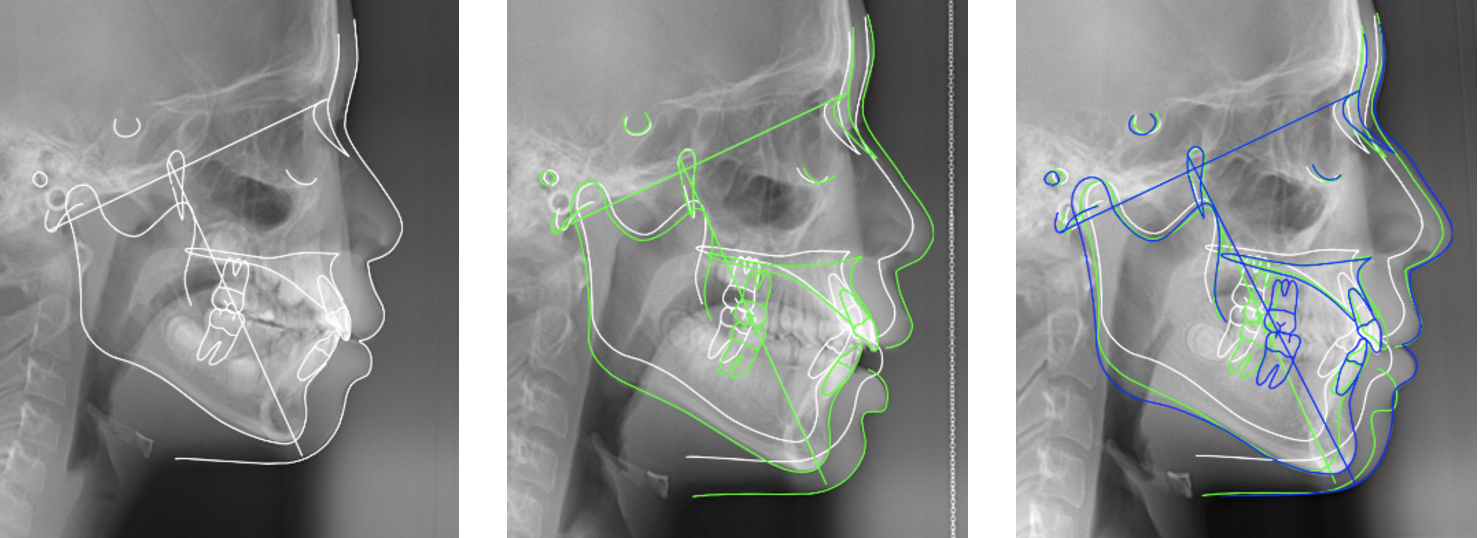

ヒルサイドビュー矯正歯科の特徴は、成長期のお子様の矯正治療において、アゴの成長のタイミングを見極めた治療を実践している点です。単に歯並びを整えるだけでなく、顔立ちの将来的な変化も考慮に入れた包括的な治療を行います。また、矯正治療において重要な役割を果たす顎関節の安定性を重視し、治療開始前に十分な検査と調整を行うことで、より確実な治療結果を目指しています。

特に大切にしているのは、顔、顎関節に注目し歯の並びをその上で咬み合せていく矯正治療です。Roth先生から学んだ口腔内の歯並びと顎関節の密接な関係を治療に取り入れ、異なる次元の矯正治療を実現しております。治療計画の立案から実施まで、院長が一貫して担当いたしますので、安心して治療をお任せいただけます。

ヒルサイドビュー矯正歯科では、顎関節(TMJ)の状態を最重要視した矯正治療を提供しています。44年の臨床経験から、下アゴの位置の安定と健全な左右の顎関節の確立が、治療成功の鍵となることを見出してまいりました。顔の見え方は下顎の位置、歯の位置、オトガイの配置に大きく影響されるため、治療開始前に綿密な方向付けを行います。

MRI検査を用いて顎関節の状態を詳細に分析し、下アゴの成長時期を的確に判断します。この診断により、矯正治療の最適なスタート時期を決定し、患者様の成長に合わせた治療計画を立案いたします。特に成長期のお子様の場合、アゴの成長を促す環境を整えることを重視し、不必要な装置の使用を避け、成長を阻害しない治療を心がけています。

矯正装置には、世界標準のエッジワイズ装置(Straight Wire Appliance)を採用し、精密な歯の移動を実現します。治療中は定期的にTMJの状態を確認し、必要に応じて調整を行うことで、安定した治療結果を目指します。治療終了後も、ポジショナーとリテーナーを併用した管理を行い、治療結果の維持に努めています。ヒルサイドビュー矯正歯科の矯正治療は、歯並びの改善だけでなく、顔立ちの調和と機能的な咬み合わせの獲得を目標としています。